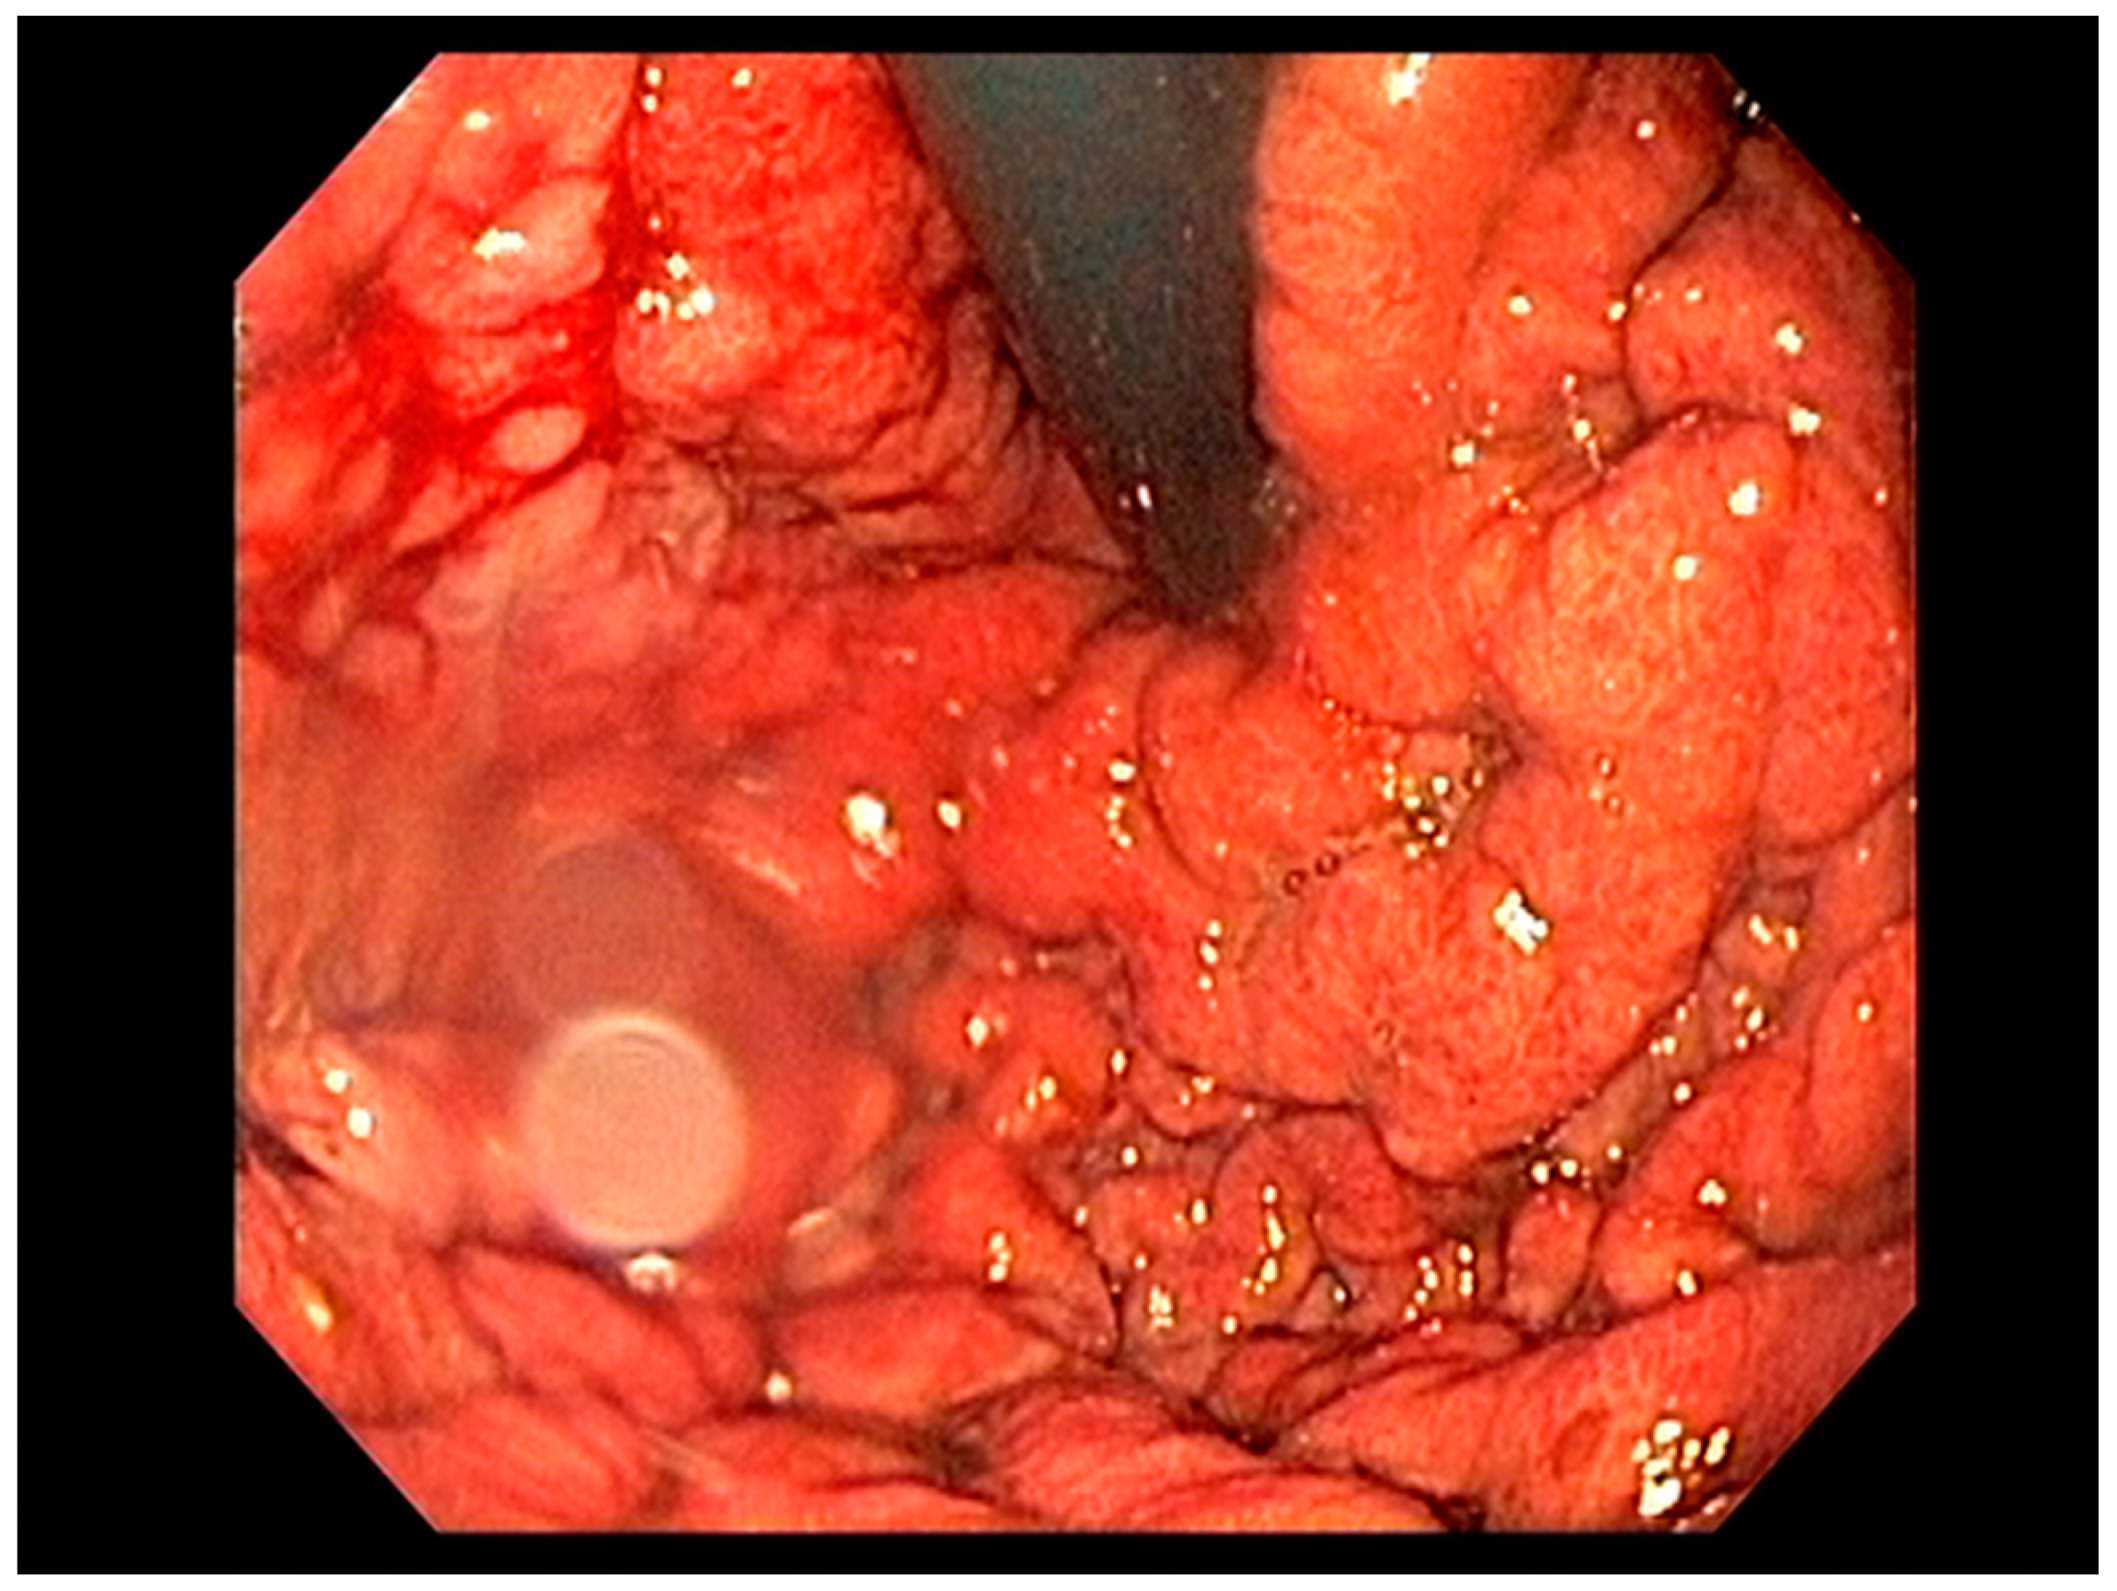

4.6. Gastric Lymphoma

- Adam, B.; Pech, O.; Steckstor, M.; Tannapfel, A.; Riphaus, A. Gastric Mucosa-Associated Lymphoid Tissue Lymphoma. Video J. Encycl. GI Endosc. 2013, 1, 174–175. [Google Scholar] [CrossRef][Green Version]

- Zullo, A.; Hassan, C.; Cristofari, F.; Andriani, A.; De Francesco, V.; Ierardi, E.; Tomao, S.; Stolte, M.; Morini, S.; Vaira, D. Effects of Helicobacter pylori Eradication on Early Stage Gastric Mucosa–Associated Lymphoid Tissue Lymphoma. Clin. Gastroenterol. Hepatol. 2010, 8, 105–110. [Google Scholar] [CrossRef] [PubMed]

- El-Zahabi, L.M.; Jamali, F.R.; El-Hajj, I.I.; Naja, M.; Salem, Z.; I Shamseddine, A.; El Saghir, N.S.; Zaatari, G.; Geara, F.; Soweid, A.M. The value of EUS in predicting the response of gastric mucosa–associated lymphoid tissue lymphoma to Helicobacter pylori eradication. Gastrointest. Endosc. 2007, 65, 89–96. [Google Scholar] [CrossRef] [PubMed]